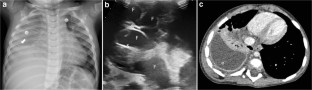

Fig. 1

Fig. 2

Fig. 3